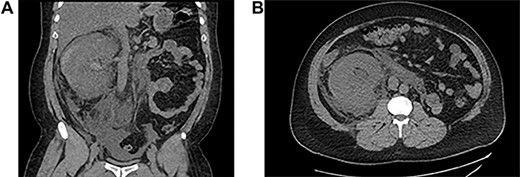

He underwent ureteroscopy and removal of ureteric stent which was inserted 3 weeks ago for an upper ureteric radiolucent stone in another hospital. The patient did not report passing the stone but ureteroscopy was negative. During his recovery after ureteroscopy and stent removal the patient developed right flank pain on Day 1 postoperative and presented to initial hospital, and was discharged from the emergency department on oral analgesics. On the third day he presented to our hospital with anuria and shortness of breath and generalized edema. His laboratory finding showed creatinine level at presentation was 735. Computed tomography (CT) abdomen without contrast showed a subcapsular hematoma with mild hydronephrosis (Fig 1). The patient was taken for percutaneous drainage using 8 Fr nephrostomy tube which drained hematouric urine with clots of 1.5 L (Fig. 2). Post drainage the patient had good urine output and the creatinine level dropped to 492. He was monitored for possible postobstructive diuresis which was anticipated and managed. He recovered his renal functions and creatinine level went back to normal levels with good urine output. On the third day the nephrostomy tube was clamped, and the patient was voiding freely with no flank pain or leak. The nephrostomy tube was removed, and he was discharged. A follow-up CT after 1 month showed complete resolution of the hematoma and the renal profile was normal.